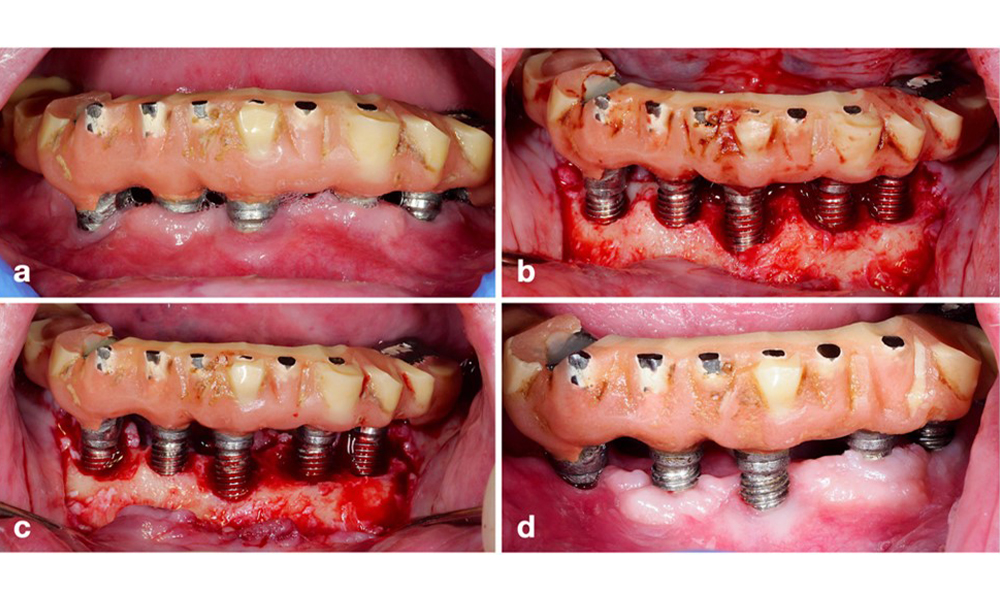

L'étendue du défaut, la position de l'implant et son importance stratégique déterminent si un implant peut ou doit être traité. Comme dans le cas d'un implant non traitable (sans espoir), un implant gravement atteint dans une restauration à plusieurs éléments peut ne pas être traité, car sa perte ne compromet pas la restauration prothétique. Par conséquent, il est conseillé d'envisager l'explantation soit au moment du diagnostic, soit au cours de l'intervention chirurgicale (figure 8).

Explantation d'un implant gravement atteint à l'aide d'un dispositif de chirurgie piézoélectrique. L'implant en position 43 faisait partie d'un bridge à 4 éléments soutenu par 3 implants. En raison d'une perte osseuse importante et d'une pertinence mineure dans le support du bridge, le traitement de l'implant a été jugé irréalisable. L'explantation a été réalisée à l'aide d'un appareil de chirurgie piézoélectrique et d'inserts spécialement conçus (a-c), ce qui a permis de réduire au minimum la perte osseuse (d).

Figure 8. Explantation d'un implant gravement atteint à l'aide d'un dispositif de chirurgie piézoélectrique. L'implant en position 43 faisait partie d'un bridge à 4 éléments soutenu par 3 implants. En raison d'une perte osseuse importante et d'une pertinence mineure dans le support du bridge, le traitement de l'implant a été jugé irréalisable. L'explantation a été réalisée à l'aide d'un appareil de chirurgie piézoélectrique et d'inserts spécialement conçus (a-c), ce qui a permis de réduire au minimum la perte osseuse (d).